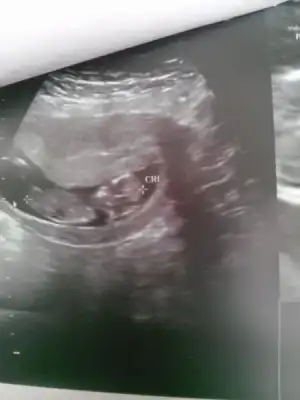

benim ilk bebeğim olacak kismetse o yüzden cinsiyet çok önemli değil aslında ama kiz olursa çok seviniriz :) senin de inşallah gönlüne gore olur belirgin bir cikinti olsaydi yanilma payi olmuyor pek ama bizimki belli olmadigi için bende emin olamiyorum ama kiza daha yakin sanirim

kiz gibi geldi bana ;)

rosechina 12 haftalikken daha ne belli olur onu da görelim de öyle netleşelim ama tabi hepsi tahmin gibi bişi kesin degil )